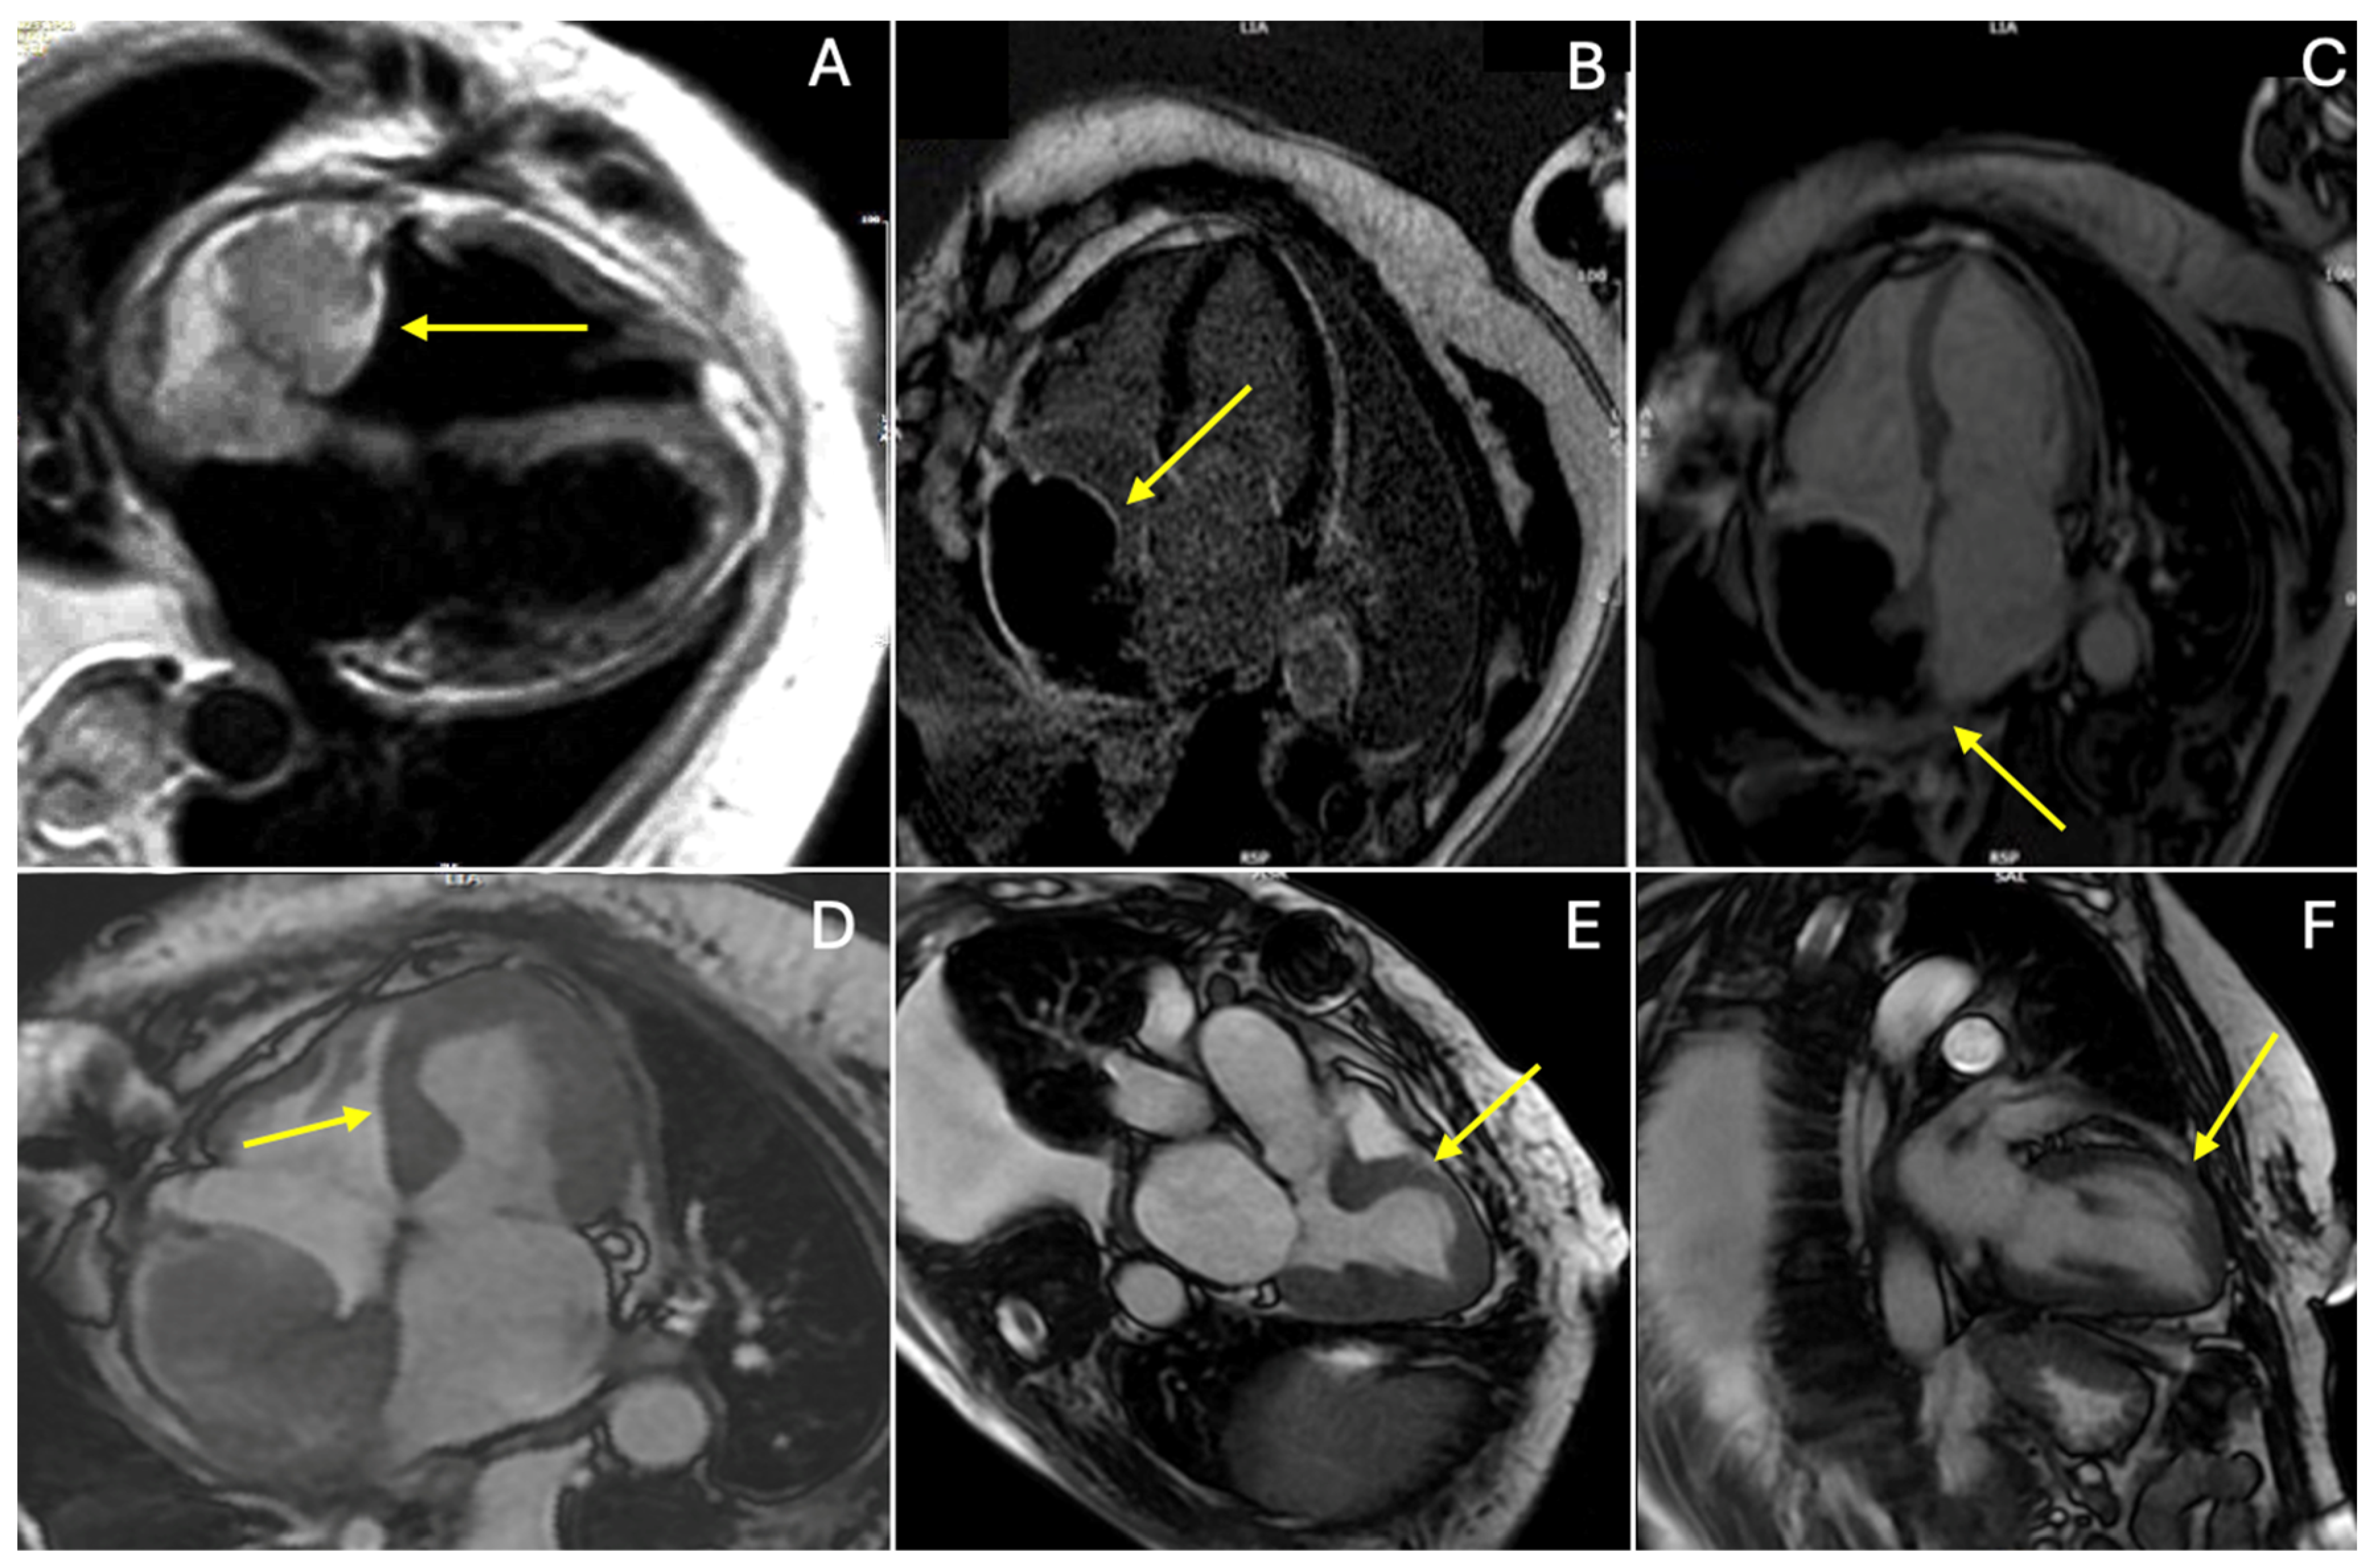

2. Case Presentation

3. Discussion